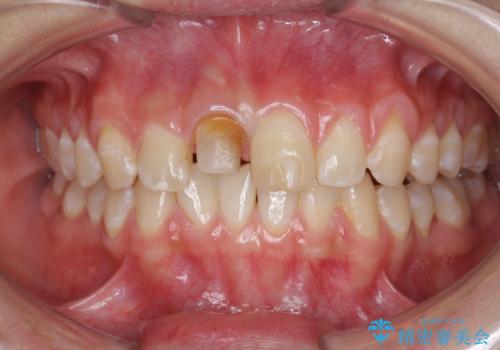

前歯をきれいにしたい ジルコニアクラウンによる審美治療

- 前歯の見た目の改善を求めて来院されました。

ジルコニアクラウンによる審美性の改善を計画します。

失活歯のため捻転を改善し、根管治療は特に希望されなかったのでそのままとしました。

今回失活歯であったため捻転を取り反対側の前歯に揃えて補綴を行うことができました。